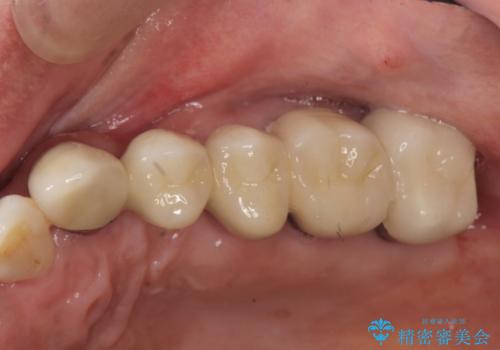

歯列不正による第一小臼歯の骨吸収が認められ、機能咬合力の回復、大きな側方力に連結することで抵抗することのできるブリッジ補綴を選択しました。

- 32万円(仮歯・フルジルコニアクラウン×4)費用は治療当時の料金となります

歯周病による深いポケット・大きな側方力・短い臨床歯根・欠損の補綴、これらの問題を解決するために歯周補綴を兼ねたブリッジを選択しました。